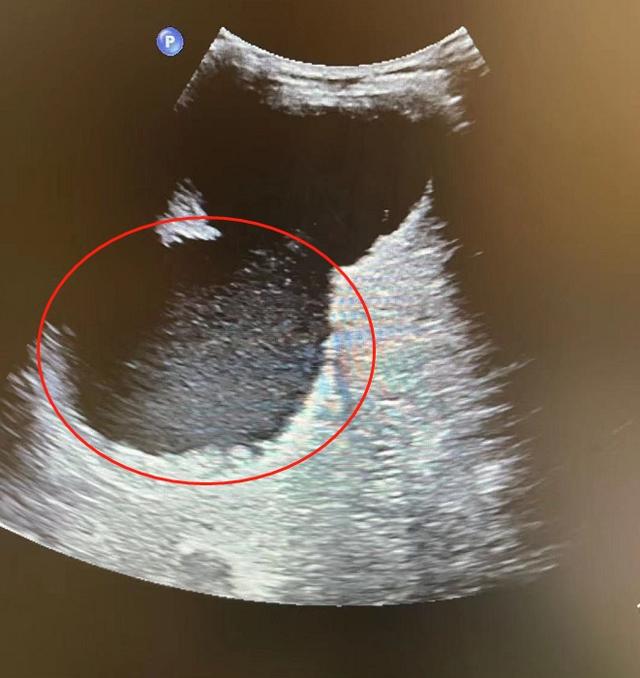

今年55岁的卞阿姨(化名)一年前发现自己的右上腹有一个很大的凸起。从那以后,她不仅每天食欲不振,还慢慢影响了呼吸。8月30日,深圳市第三人民医院(南科大二附院)为边女士做了超声波检查,发现其肝脏上长了一个...